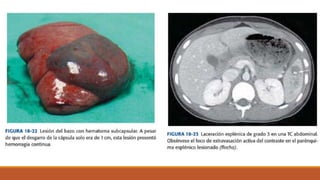

En pacientes estables, la T C abdominal con contraste IV es la prueba principal para diagnosticar

y caracterizar las lesiones del bazo.

• Las lesiones esplénicas aparecen como interrupciones del parénquima esplénico normal, se identifica

extravasación activa del contraste, presente en forma de mancha hiperdensa o sangrando al espacio

peritoneal.

Otros hallazgos: hematoma confinado al espacio subscapsular o desvascularización completa del

órgano